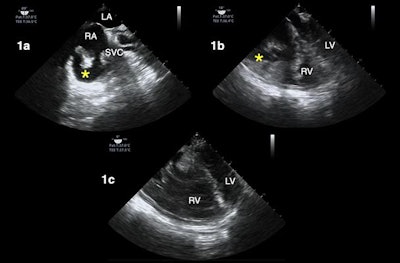

Other use cases for TEE include evaluating the heart and lungs of patients who must stay in a prone position and those experiencing shock, a finding not uncommon in hospitalized patients with COVID-19, according to the authors.

"We have found that the TEE exam in prone patients has been particularly helpful during the COVID pandemic, given the degree of hypoxemia seen in these patients and the many urgent ECMO evaluations we've had to perform," the authors wrote.